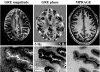

The ability to detect brain anatomy and pathophysiology with MRI is limited by the contrast-to-noise ratio (CNR), which depends on the contrast mechanism used and the spatial resolution. In this work, we show that in MRI of the human brain, large improvements in contrast to noise in high-resolution images are possible by exploiting the MRI signal phase at high magnetic field strength. Using gradient-echo MRI at 7.0 tesla and a multichannel detector, a nominal voxel size of 0.24 x 0.24 x 1.0 mm3 (58 nl) was achieved. At this resolution, a strong phase contrast was observed both between as well as within gray matter (GM) and white matter (WM). In gradient-echo phase images obtained on normal volunteers at this high resolution, the CNR between GM and WM ranged from 3:1 to 20:1 over the cortex. This CNR is an almost 10-fold improvement over conventional MRI techniques that do not use image phase, and it is an approximately 100-fold improvement when including the gains in resolution from high-field and multichannel detection. Within WM, phase contrast appeared to be associated with the major fiber bundles, whereas contrast within GM was suggestive of the underlying layer structure. The observed phase contrast is attributed to local variations in magnetic susceptibility, which, at least in part, appeared to originate from iron stores. The ability to detect cortical substructure from MRI phase contrast at high field is expected to greatly enhance the study of human brain anatomy in vivo.